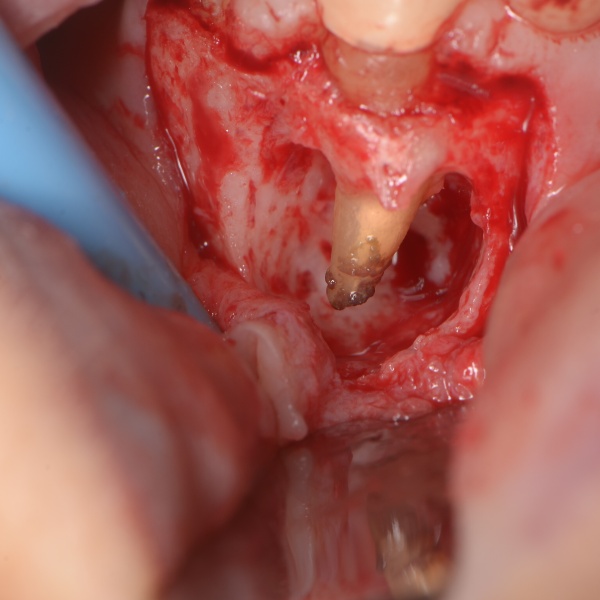

Retrográdní chirurgická endodoncie

11. 11.

MDDr. Radovan Žižka, Ph.D., MSc.

Co vás na online přednášce čeká?

I přes vysokou úspěšnost endodontického ošetření se v praxi setkáváme s případy selhání a často řešíme otázku:

„Zvolit reendodontické ošetření, retrográdní chirurgickou endodoncii, nebo zub extrahovat?“

V přednášce se pokusíme vnést do rozhodování více jasno.

• Příčiny selhání endodontického ošetření a jasná kritéria, kdy je vhodná retrográdní chirurgická endodoncie.

• Rozdíl mezi resekcí kořenového hrotu a retrográdní chirurgickou endodoncií; kdy je i dnes na místě samostatná resekce kořenového hrotu.

• Praktický, krok-za-krokem návod pro prediktabilní provedení:

• od anestezie

• až po suturu

(pro začátečníky a mírně pokročilé)

• Řada kazuistik včetně hraničních případů

(pro pokročilé a velmi pokročilé)